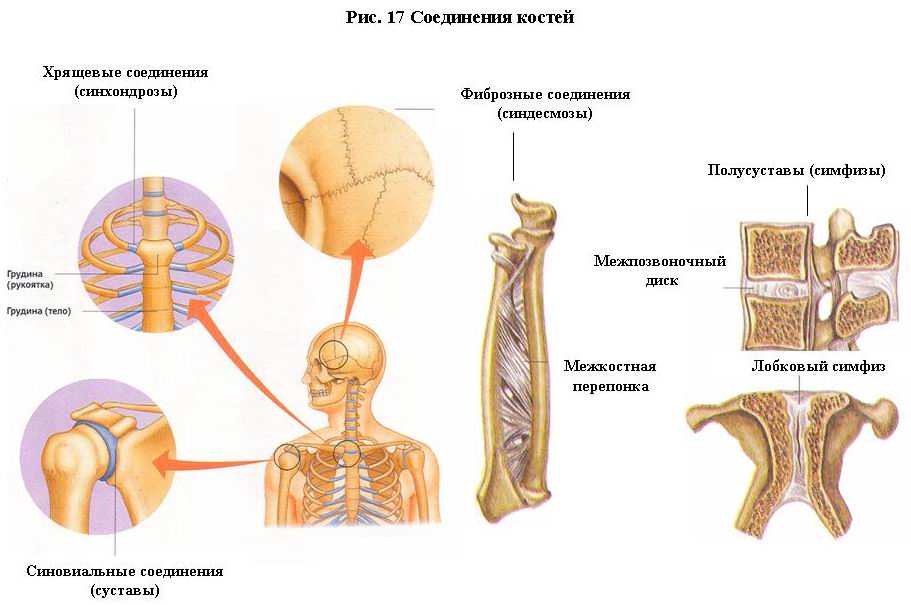

Диаграммы и схемы движения в суставах человека